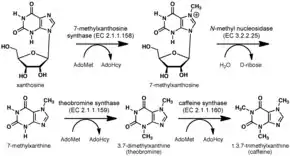

The biosynthesis of caffeine is an example of convergent evolution among different species.[202][203][204]